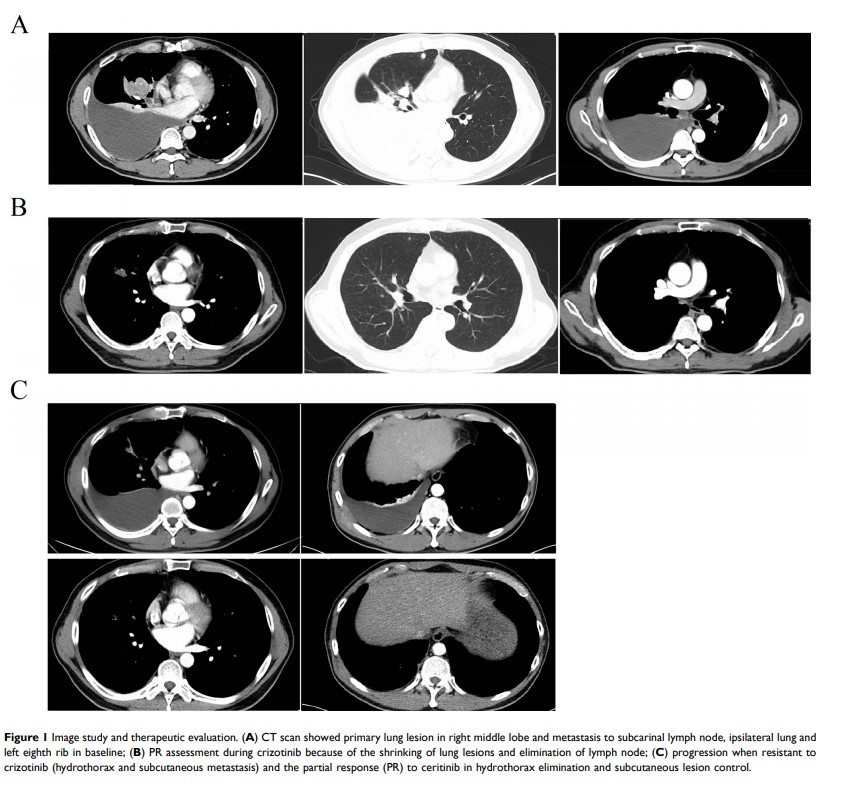

伴重排丢失的肺腺癌在克唑替尼和赛瑞替尼治疗期间 COX7A2L–ALK 、LINC01210–ALK 、ATP13A4–ALK 及获得性 SLCO2A1–ALK 共存:一份病例报告